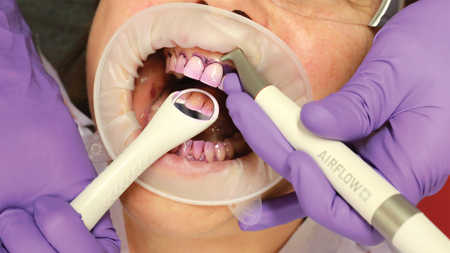

A New Tool for Cleaning Excess Resin Cement

Cleaning excess cement after cementation of a crown is a tedious but important clinical procedure. Failure to remove excess cement can lead to plaque accumulation, gingival inflammation and possibly even bone loss.1 Removal of cement is even more difficult when using resin cement. A recent Practice Based Research Network study reported that almost 40 percent … Read more